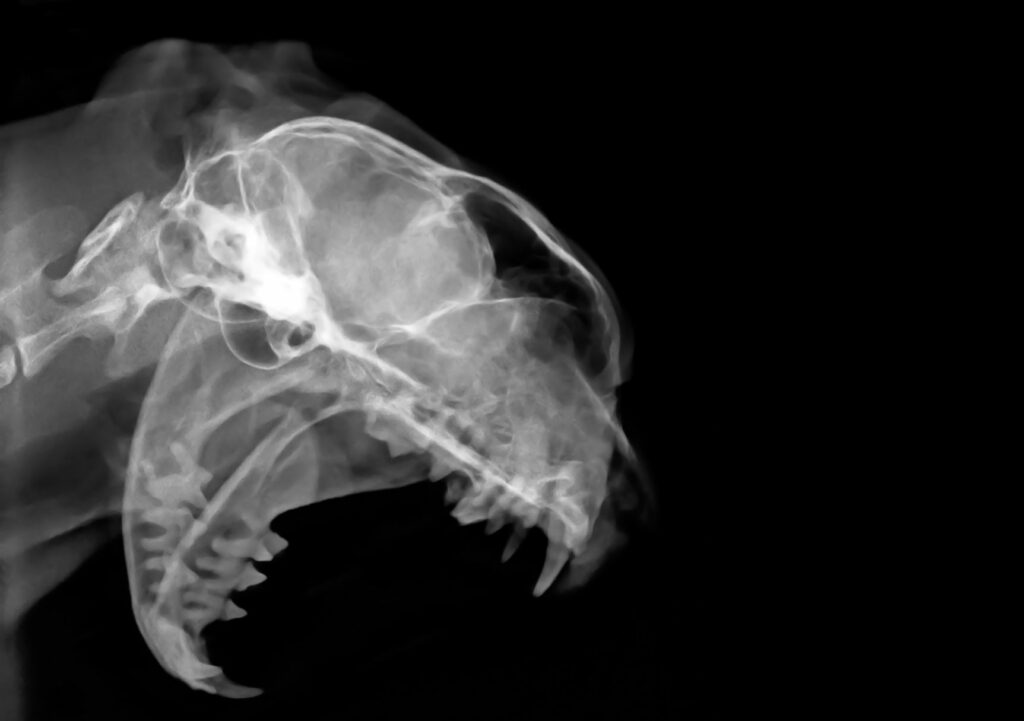

Katzenanatomie durchscheinend in drei Phasen 1. Skelett, 2. Organe,3. Muskulatur. Die Hauskatze